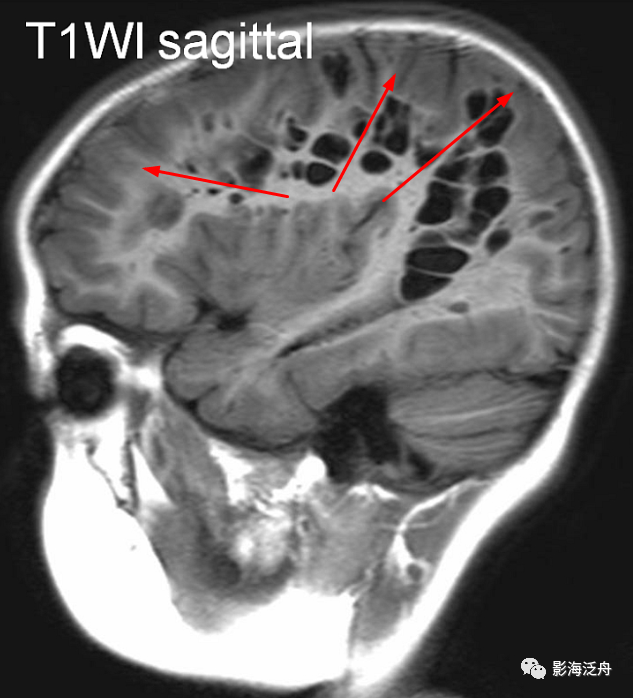

II型-大脑半球型:扩大VR腔隙呈对称性广泛分布于双侧半卵圆中心及皮层下白质区域(黄箭),少位于扣带回旁(白箭),部分呈类圆形(红箭头),部分呈裂隙样/线样(蓝箭头),注意绿箭头所指的VR腔隙边缘可见Flair高信号影,这种高信号可能是局部液体少量渗漏造成的。